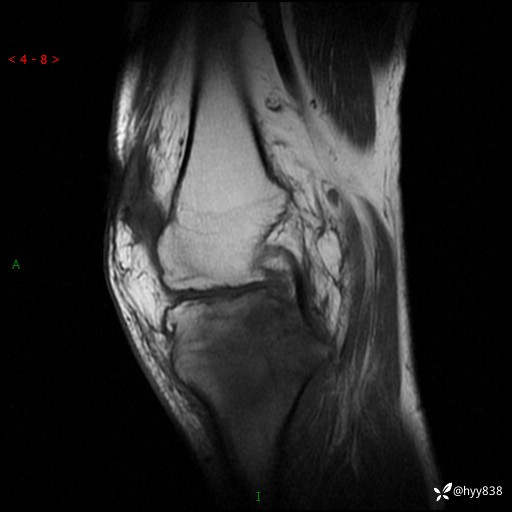

MRI(sag :T1WI+T2WIfs)